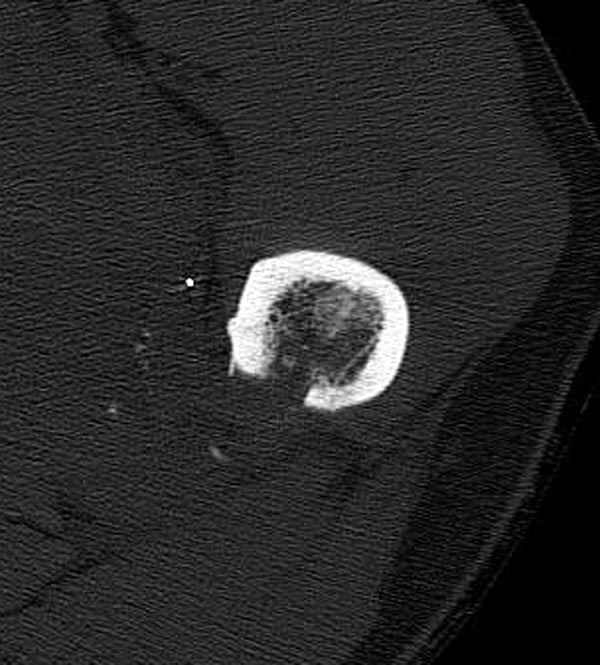

Больной с огнестрельным переломом бедра с вовлечением около 15% медиального кортекса, входное отверстие около 1 см в диаметре; стабильный, без сосудистых и неврологических признаков.

Входные маленькие отверстия от ранении просто игнорируются, никаких дренажей, как любое колотое ранения, они закрываются и были случаи через месяц. Конечно, ведется профилактика открытых ранении: сыворотки и т.д., но еще самое главное уделяем профилактике образования перелома из-за стресса в результате дефекта кортикального слоя.

Литературные данные о влиянии кортикального дефекта на стрессовые переломы в длинных трубчатых костях в основном встречаются в онкологии, например кортикальный дефект более 50% имеет больше шанса стрессовых переломов, чем в нашем случае.

Учитывая, что больной получил травму не во время визита в церковь, и он является одним из представителем 40 миллионного “outstanding itizen”, без медицинской страховки, без работы в свои 39 лет, и без надлежающей ортопедической дисциплины у которого отсутсвует страх стрессового перелома, было рекомендовано оперативное лечение: профилактическое антеградное интрамедуллярное штифтование.

Методика штифтования при отсутствии большой зоны перелома как при онкологических профилактических штифтованиях, расверливание интрамедуллярного канала проводим с предварительным наложением дополнительного дренажного отверстия в дистальном отделе бедра (в данном случаи в канале оставили 6.5 мм канюлированный шуруп), иначе при создании давления в канале во время сверления имеется опасность эмболизации легочной артерии тромбом.